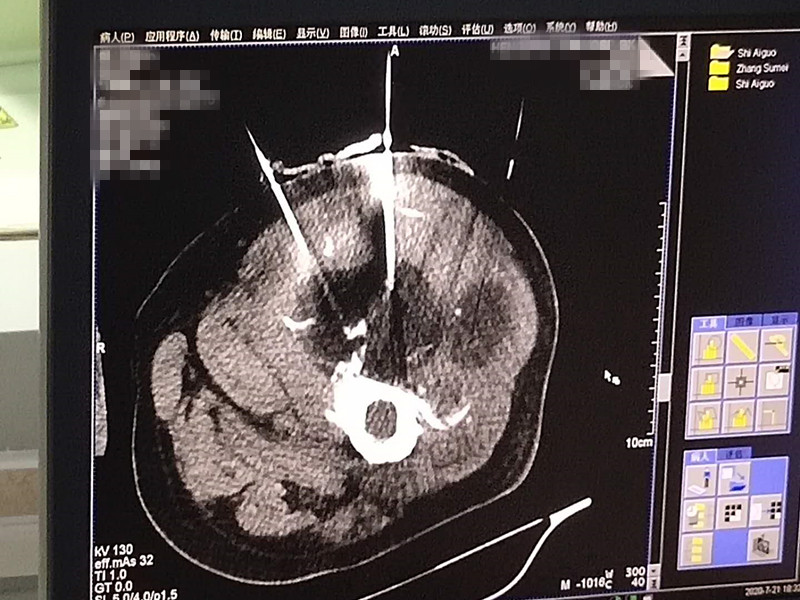

75岁腿部软组织肉瘤氩氦刀冷冻消融